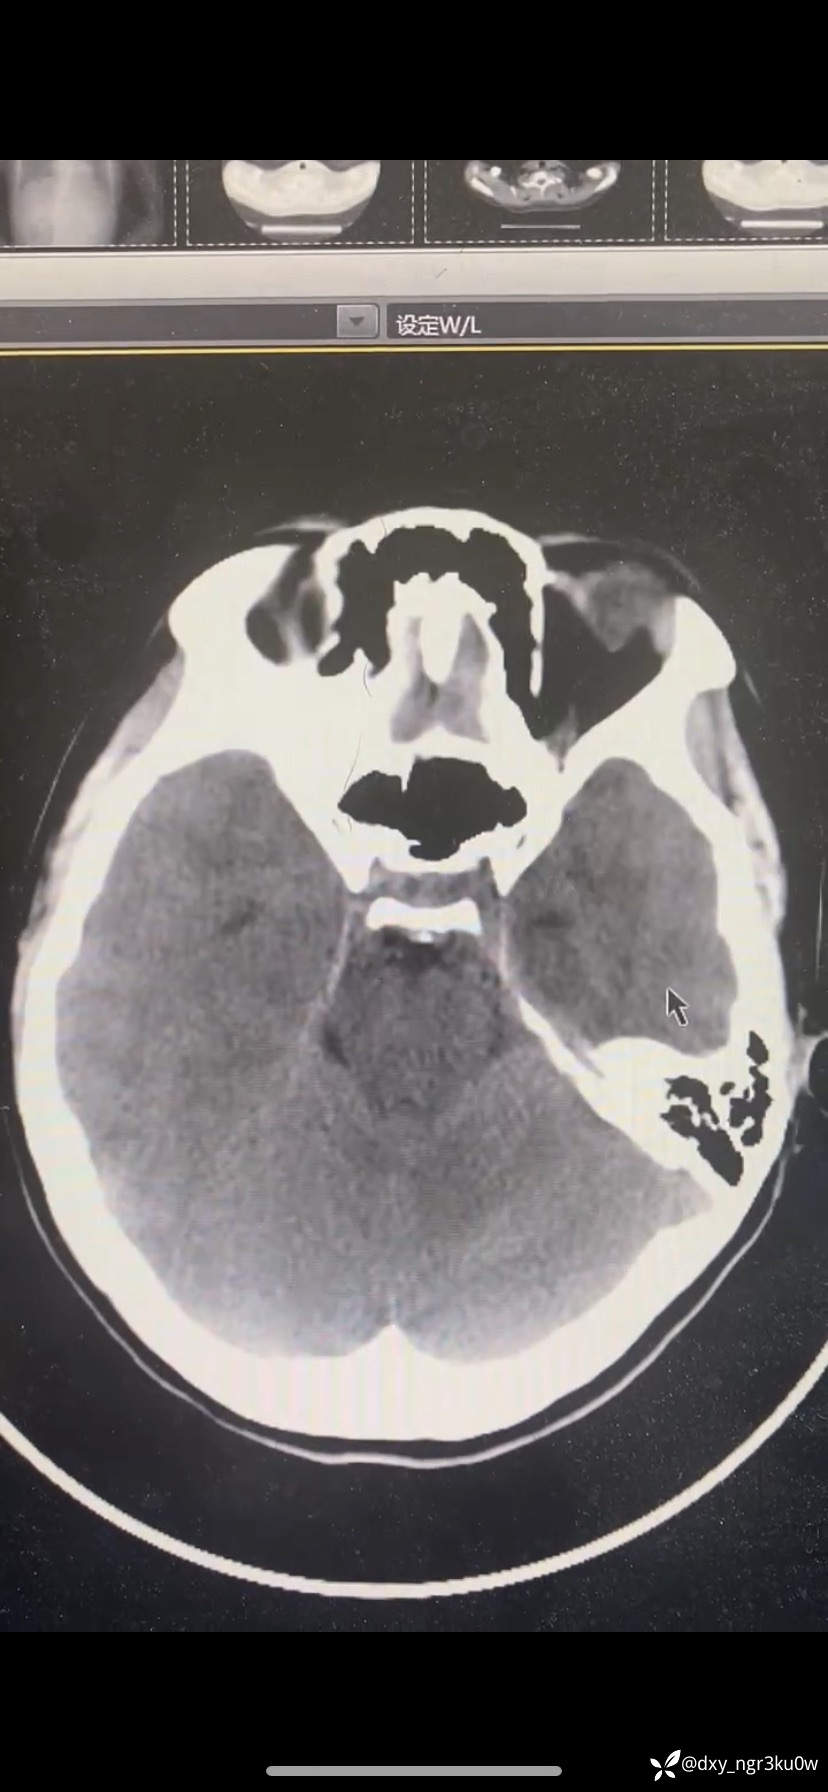

入院血气分析:ph:7.001,PCO2 10.7,PO2 136.6,Na124,K5.18,HCO3- 2.6,Glu>30,Lac1.7。颅脑CT如下